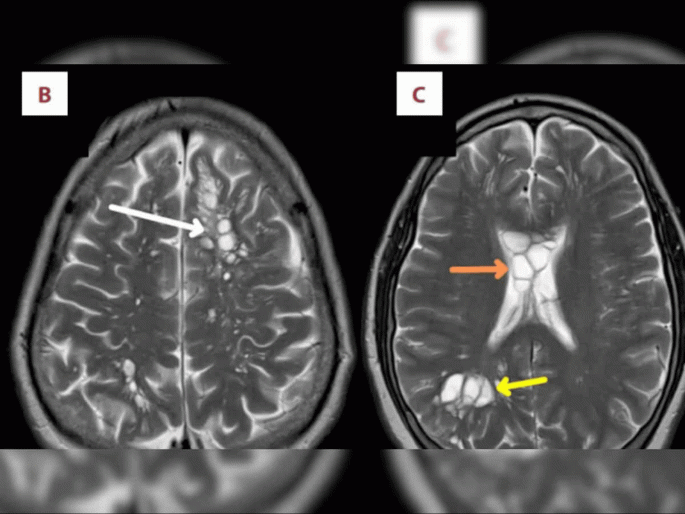

स्कॅनमधून समोर आलं की, पीडित व्यक्तीच्या मेंदुमध्ये टेपवर्मचा लार्वल सिस्ट आहे जो सिस्टिसिरोसिस (Cysticercosis) आजाराचं कारण ठरला.

बीबीसीच्या रिपोर्टनुसार, स्कॅनमधून समोर आलं की, पीडित व्यक्तीच्या मेंदुमध्ये टेपवर्मचा लार्वल सिस्ट आहे जो सिस्टिसिरोसिस (Cysticercosis) आजाराचं कारण ठरला. डॉक्टरांचं मत आहे की, ही समस्या चांगल्या पद्धतीने हात न धुण्यासंबंधी आहे आणि अशीही शक्यता आहे की, रूग्णाने अर्धा शिजलेला बेकन खाल्ला होता. जो इन्फेक्शनचं कारण आहे.

सिस्टिसिरोसिस एक प्रकारचं इन्फेक्शन आहे जे पॅरासाइट टेनिया सोलियम (Taenia Solium) च्या लार्वामुळे होतं. ज्याला पोर्क टॅपवार्म (Pork Tapeworm) असंही म्हटलं जातं. ज्यामुळे मेंदुमध्ये सिस्ट विकसित होऊ शकतं. टॅपवार्म असलेली कोणतीही व्यक्ती स्वत:ला टॅपवार्म अंड्यांनी संक्रमित करू शकते. ही एक प्रक्रिया ऑटोइन्फेक्शन (Autoinfection) म्हणून ओळखली जाते. जी शरीरातून वेस्टच्या रूपात बाहेर निघू शकते आणि त्याच घरातील इतरांना संक्रमित करू शकते.

अमेरिकन जर्नल ऑफ केस रिपोर्ट्समध्ये या केसबाबत डॉक्टरांनी लिहिलं की, केवळ अंदाज लावला जाऊ शकतो, व्यक्तीच्या सिस्टिसिरोसिसला योग्यपणे हात न धुतल्यानंतर ऑटोइन्फेक्शनच्या माध्यमातून ट्रांसमिट केलं गेलं होतं. या केसबाबत सांगायचं तर 52 वर्षीय रूग्णाच्या डॉक्टरांना वाटतं की, इटिंग हॅबिट्स यासाठी जबाबदार आहे. रूग्णाने अॅंटी-पॅरासायटिक आणि अॅंटी इंफ्लेमेंट्री मेडिकेशनला रिस्पॉन्ड केलं आणि तो पूर्णपणे बरा झाला.